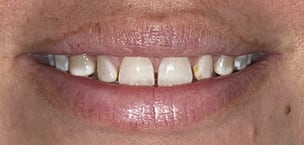

A 46-year-old female patient presented with the chief complaint of disliking the shape, color, and spacing of her front teeth. After conducting online research, the patient was adamant she did not want veneers or traditional bonding but instead preferred Bioclear® composite restorations (Bioclear, bioclearmatrix.com) on her maxillary and mandibular anterior teeth to preserve tooth structure. An intraoral scan using the iTero Element® 2 intraoral scanner (Align Technology, Inc, itero.com) and photographs were taken. It was discussed with the patient that prior to final restorations Invisalign® clear aligner therapy (Align Technology, Inc, invisalign.com) was needed to close all mandibular spacing (eliminating the need for restorations) and partially close the maxillary spacing (improving the height-to-width ratios of the final maxillary restorations). The patient completed Invisalign treatment in 15 weeks and then whitened with Opalescence™ PF 10% whitening gel (Ultradent, ultradent.com). An intraoral scan with the iTero Element 2 scanner was taken for a pre-prosthetic lab wax-up of teeth Nos. 6 through 11. These teeth were restored with full esthetic composite veneers using the Bioclear heated composite injection overmolding technique with Filtek™ Supreme Ultra Universal Restorative White Body paste and flowable (3M Oral Care, 3m.com). No tooth structure was resected. The patient was immediately scanned for Vivera® retainers. She was thrilled with her smile transformation.

Direct composite restorations with the Bioclear method

are minimally invasive, additive, and esthetically natural looking.